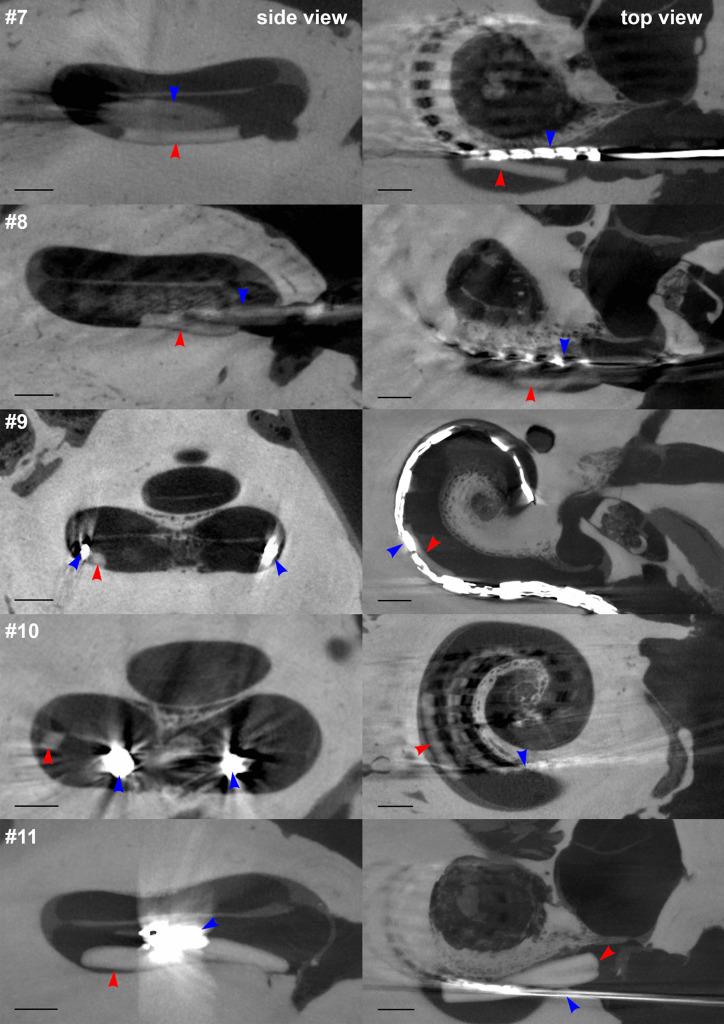

The effective delivery of drugs to the inner ear is still an unmet medical need. Local controlled drug delivery to this sensory organ is challenging due to its location in the petrous bone, small volume, tight barriers, and high vulnerability. Local intracochlear delivery of drugs would overcome the limitations of intratympanic (extracochlear) and systemic drug application. The requirements for such a delivery system include small size, appropriate flexibility, and biodegradability. We have developed biodegradable PLGA-based implants for controlled intracochlear drug release that can also be used in combination with cochlear implants (CIs), which are implantable neurosensory prosthesis for hearing rehabilitation. The drug carrier system was tested for implantation in the human inner ear in 11 human temporal bones. In five of the temporal bones, CI arrays from different manufacturers were implanted before insertion of the biodegradable PLGA implants. The drug carrier system and CI arrays were implanted into the scala tympani through the round window. Implanted temporal bones were evaluated by ultra-high-resolution computed tomography (µ-CT) to illustrate the position of implanted electrode carriers and the drug carrier system. The µ-CT measurements revealed the feasibility of implanting the PLGA implants into the scala tympani of the human inner ear and co-administration of the biodegradable PLGA implant with a CI array.

将药物有效递送至内耳仍然是一个未满足的医学需求。由于其位于颞骨内、体积小、屏障紧密且易受损,因此向该感觉器官进行局部控释药物递送极具挑战性。局部内耳内(耳蜗外)药物递送将克服鼓室内(耳蜗外)和全身药物应用的局限性。这种递药系统的要求包括体积小、适当的柔韧性和生物降解性。我们已经开发出基于可生物降解的 PLGA 的植入物,用于控制内耳内药物释放,也可与可植入神经感觉假体(用于听力康复的耳蜗植入物)联合使用。该药物载体系统已在 11 个人类颞骨中进行了内耳植入测试。在其中 5 个人类颞骨中,在插入可生物降解的 PLGA 植入物之前,已植入了来自不同制造商的 CI 阵列。药物载体系统和 CI 阵列通过圆窗被植入到鼓阶。通过超高分辨率计算机断层扫描(µ-CT)对植入的颞骨进行评估,以说明植入电极载体和药物载体系统的位置。µ-CT 测量结果表明,将 PLGA 植入物植入人类内耳的鼓阶并与 CI 阵列联合给药具有可行性。